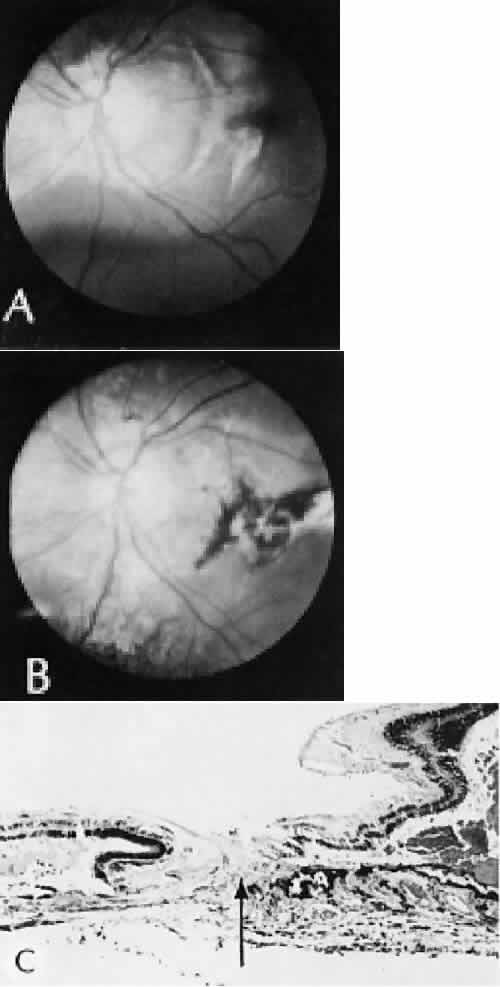

Retinal detachment (Fig. 42) occurs in approximately 2% to 8% of intracapsular cataract surgeries, compared with approximately 0.0013% in the general population. The incidence of retinal detachment after extracapsular cataract extraction and posterior chamber lens implantation ranges between 0.6% and 1.5%.121 Vitreous loss increases the incidence of postoperative detachments, particularly if there is vitreous incarceration into the cataract wound. The character of the retinal detachment is independent of the type of cataract surgery or the type of intraocular lens implanted. However, a lower incidence of proliferative vitreoretinopathy appears in cases of extracapsular cataract extraction than was formerly seen with intracapsular cataract extraction.

Fig. 42. Two cases of retinal detachment following cataract extraction. A. Retinal detachment was identified 4 weeks after cataract extraction. Fixed retinal folds indicate that the situation is inoperable, so no surgical repair was attempted. The anterior chamber angle has become occluded because of neovascularization associated with ischemic retina. B. Retinal detachment was identified 5 weeks after cataract extraction. Two attempts at surgical repair failed. The large equatorial cystic spaces indicated the presence of a scleral-buckling element. The actual material of the sponge and buckle has been lost during tissue processing. The cystic nature of the detached retinal tissue indicates that there was an extended time between the last retinal reattachment attempt and enucleation. In this case, peripheral anterior synechiae are present. The indication for enucleation was most likely a blind painful eye due to secondary glaucoma and reactive uveitis. (Hematoxylin-eosin stain; × 3.)